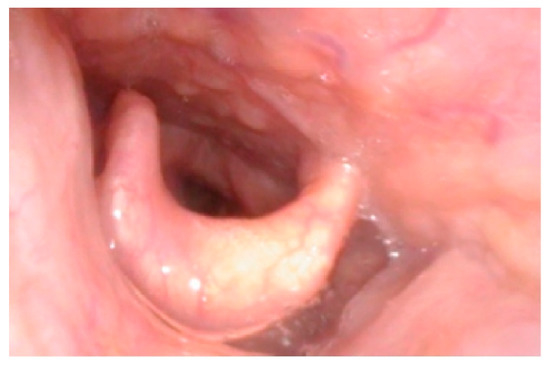

- Gadepalli, C.; Tol, G.; Yadthore, S.; Sharma, R.; Jovanovic, A.; Palmer, J.; Stepien, K.M. Nasendoscopy findings in adult patients with mucopolysaccharidosis: A tertiary UK centre experience. Mol. Genet. Metab. 2020, 129, S59–S60. [Google Scholar] [CrossRef]